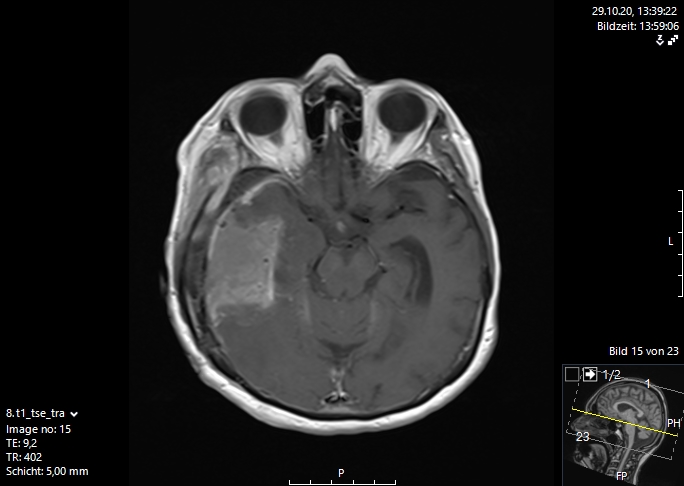

Η μαγνητική τομογραφία εγκεφάλου είναι η μέθοδος εκλογής για την απεικόνιση των εγκεφαλικών μεταστάσεων. Αυτή διενεργείται είτε επί υποψίας αλλοίωσης στο κεντρικό νευρικό σύστημα, λόγω ανάπτυξης μιας νευρολογικής συμπτωματολογίας ή απλά στα πλαίσια του γενικού staging με τακτικές απεικονίσεις στο σώμα και στον εγκέφαλο. Με τη βοήθεια αυτής της απεικονιστικής διαδικασίας μπορεί να γίνει ορατός ο παθολογικά αλλοιωμένος εγκεφαλικός ιστός με τις νεκρώσεις του καθώς και το περιεστιακό εγκεφαλικό οίδημα (συσσώρευση νερού στον εγκέφαλο).

Σήμερα υπάρχουν διάφορες διεγχειρητικές τεχνικές, που μας υποστηρίζουν στο στόχο μας, να αφαιρέσουμε όσο περισσότερο καρκινικό ιστό , αν γίνεται ιστό ακόμα και από την περιοχή γύρω από τον όγκο, που ονομάζουμε διηθητική ζώνη. Μερικές σύγχρονες διεγχειρητικές τεχνικές, είναι η νευροπαρακολούθηση, η νευροπλοήγηση με απεικόνιση των δεσμίδων, η ενδοσκοπική νευροχειρουργική και τα χειρουργεία με ασθενή σε εγρήγορση. Ο συνδυασμός λοιπόν ενός ασφαλούς χειρουργείου με ταυτόχρονη ολική αφαίρεση του όγκου αποτελεί τον στόχο της σύγχρονης χειρουργικής νευρο-ογκολογίας και στην περίπτωση των εγκεφαλικών μεταστάσεων. Οι εικόνες 1 και 2 απεικονίζουν μια ολική εξαίρεση μιας μετάστασης δεξιά κροταφικά. Αυτό είναι σαφέστατα πιο πιθανό να προσφερθεί από ειδήμονες νευροχειρουργούς (Gousias K, 2024) με ειδική εκπαίδευση σε μεγάλα κέντρα, μεγάλη χειρουργική εμπειρία και εξειδίκευση στην χειρουργική των όγκων καθώς και διεθνή αναγνώριση τους. Η επιτροπή Χειρουργικής Νευρο-ογκολογίας της Ευρωπαϊκής Νευροχειρουργικής Εταιρείας δημοσίευσε το προφίλ ενός expert χειρουργού για όγκους εγκεφάλου και νωτιαίου μυελού (Gousias K, 2024).